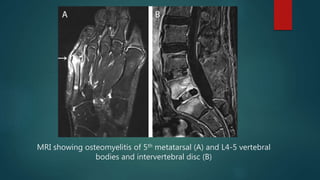

๏ต MRI

๏ต Highly sensitive and specific (>90%)

๏ต Good for early detection and surgical localization

๏ต Useful in differentiating bone and soft tissue infection

๏ต Limitation: A metallic implant in the region may produce

focal artifacts and can cause a safety hazard.

MRI showing osteomyelitis of 5th metatarsal (A) and L4-5 vertebral

bodies and intervertebral disc (B)